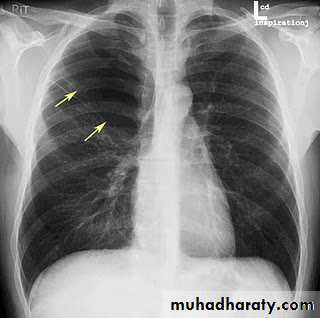

Bronchectasis

Abnormal irreversible dilatation of bronchioles with thickening of their walls . Presented with recurrent pneumonias & haemoptysis ..Types:Cystic

Fusiform

Cylendrical

In which the bronchiole is wider than the near by vascular branch

Causes –infancy & childhood infection

-TB

-pulmonary fibrosis

-cystic fibrosis

-immotile cilia syndromes